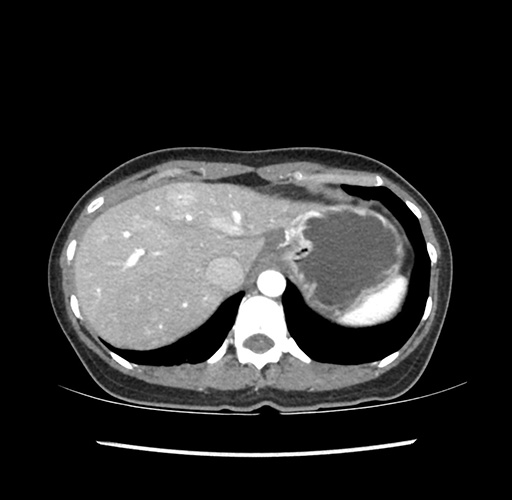

Imaging Analysis

Look through the patient's CT scan to identify any areas of concern for the necessary procedure.

Based on your CT findings, which issue(s) would give reason for "planned slowing down moment(s)" in this case?